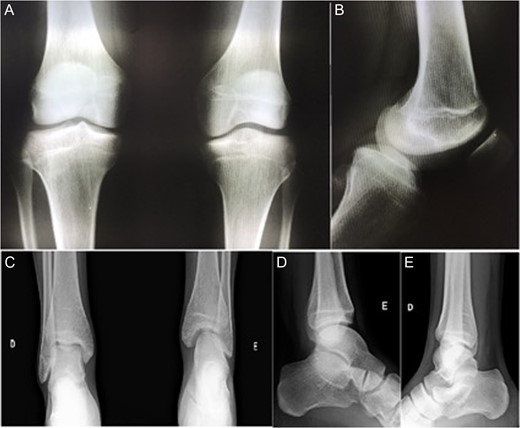

Magnetic resonance imaging (MRI) also showed bucket handle tear of the medial meniscus, complete absence of ACL and PCL, joint effusion, patellofemoral dysplasia, lateral patellar tilt and superficial patellar chondropathy (Fig. 2).

MRI of the affected knee showing the congenital absence of the cruciate ligaments (circles) and the presence of a bucket handle tear of the medial meniscus (arrow).